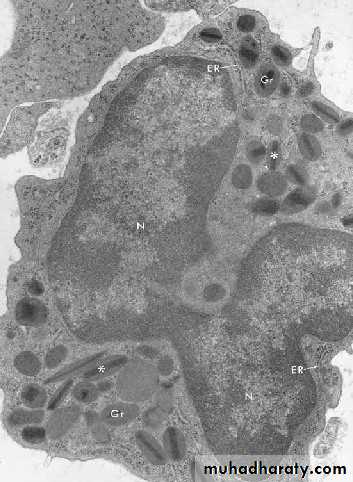

Neutrophils (PMNs)

Most numerous WBC in bloodMultilobed nucleus

Granules:

Azurophilic granules

Specific granules

Function

1st wave of cells in acute inflammation; can phagocytose bacteria